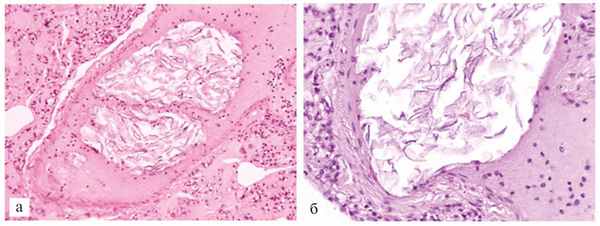

Амнион и Околоплодные Воды: Функции и Роль в Беременности